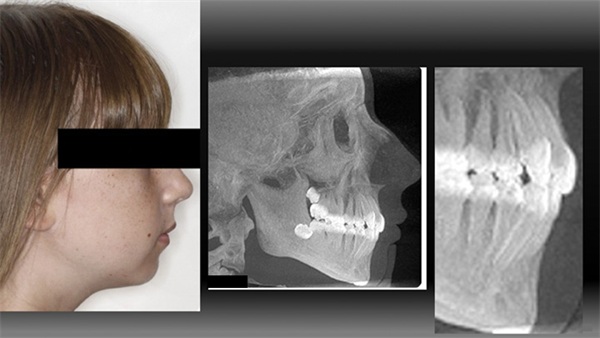

Rylee was 14 years old when she and her mom presented with a chief complaint of crowding (Fig. 1). Rylee was mildly retrognathic and presented with a Class I occlusion. Anatomically it was her lack of a chin button that really compounded the mild retrognathia to show a very deficient chin projection overall. Both arches were very crowded and she had what I would grade as thin lips. She did not show a posterior crossbite, but her maxilla appeared more narrow than ideal and the mandibular posterior teeth showed excess lingual compensation/exaggerated Curve of Wilson. Her chin projection was discussed in the exam room and she and her mom declined orthognathic and genioplasty options.

For Rylee, as with all my patients, I set my treatment goals from outside-in, and that began with her macro/facial aesthetics. In her case, high priority was given to her lips. Given the aesthetic inclination of the upper incisors (lacking ideal torque) and paired with the thin lips, my preference was to see the upper incisors roll forward slightly so that the lower two-thirds facial surface was perpendicular to Frankfort horizontal plane (Fig. 2).

After considering her macroaesthetics, we next looked at her mini/smile aesthetics. In the side smiling photograph (Fig. 3) I felt that in addition to the lack of positive torque, her upper incisors lacked ideal aesthetic projection forward (A-P) within her smile.

In Figure 10, notice her lips and in particular the fullness and increased vermilion display of her lower lip (which rests on the labial surface of the now more forward maxillary incisors).

Notice in Figure 11 the slightly more forward “projection” of her maxillary incisors within her smile. As you look at this photo, would you desire her upper incisors to be any degree further retracted from where they ended up within this face? Even a millimeter?

Finally, I ask you to look again at Figure 10. If you are not routinely looking at the lips of your patients before and after treatment, the change for Rylee here might not mean much to you and that’s ok. My intention is not to convince you that this type of lip change is important or to change your view on facial aesthetics. As practitioners, we are free to dictate our own aesthetic goals to our patients as we please. As a profession, we can choose to reject the growing evidence that our patients do in fact place a very high value on this type of lip change. We can choose to ignore the primary role that we as orthodontists play in the lip presentation of many of our patients. I hope we will not and I hope that, within reason given each unique case, we can evolve our aesthetic goals to what is favored by and what is possible for the patients that we serve.